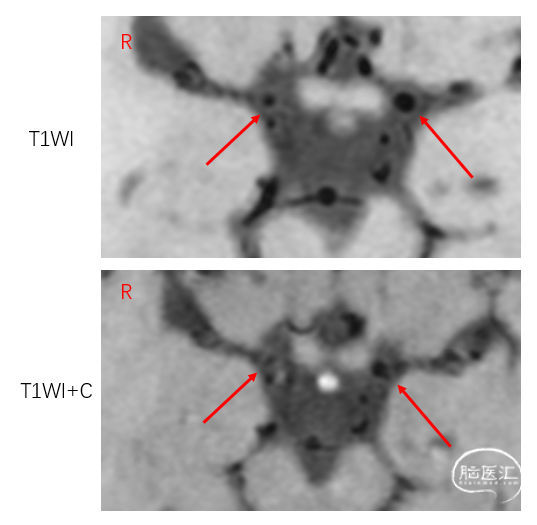

病例甲的高分核磁:显示右侧颈内动脉末端向心性狭窄,内膜增厚,无强化,符合烟雾病的表现。

病例乙的高分核磁:右侧大脑中动脉M1段呈偏心狭窄,斑块呈等T1信号,增强扫描后明显强化。

左侧大脑中动脉M1段存在下壁等信号斑块。

复习:高分核磁对烟雾病和动脉粥样硬化的鉴别诊断:

烟雾病:向心性狭窄,强化或不强化

动脉粥样硬化斑块:偏心性狭窄,T2可呈高信号,强化或不强化